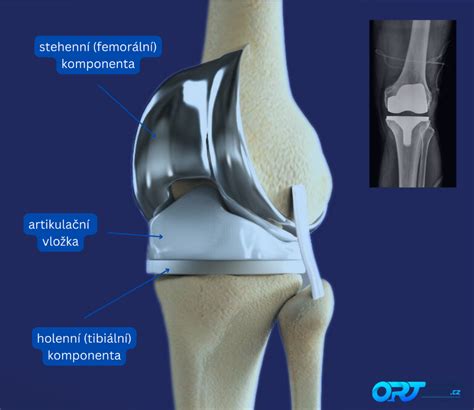

Celková endoprotéza kolena (TEP)

V niektorých prípadoch, keď konzervatívna liečba a menej invazívne zákroky nezaberajú, môže byť potrebná totálna endoprotéza kolena (TEP). Lekári posudzujú potrebu TEP komplexne, pričom zohľadňujú nielen nález na röntgenovom snímku, ale aj bolesť a obmedzenú pohyblivosť pacienta.

Priebeh TEP

Počas operácie sa odstráni chorá časť stehennej a holennej kosti, vyrovná sa osová deformita končatiny a väzivová nerovnováha kolenného kĺbu. Následne sa implantujú komponenty endoprotézy.

Komplikácie a životnosť TEP

Komplikácie sa môžu vyskytnúť pri každej operácii. Priemerná životnosť kolennej náhrady je približne 15 rokov, v závislosti od zaťaženia.